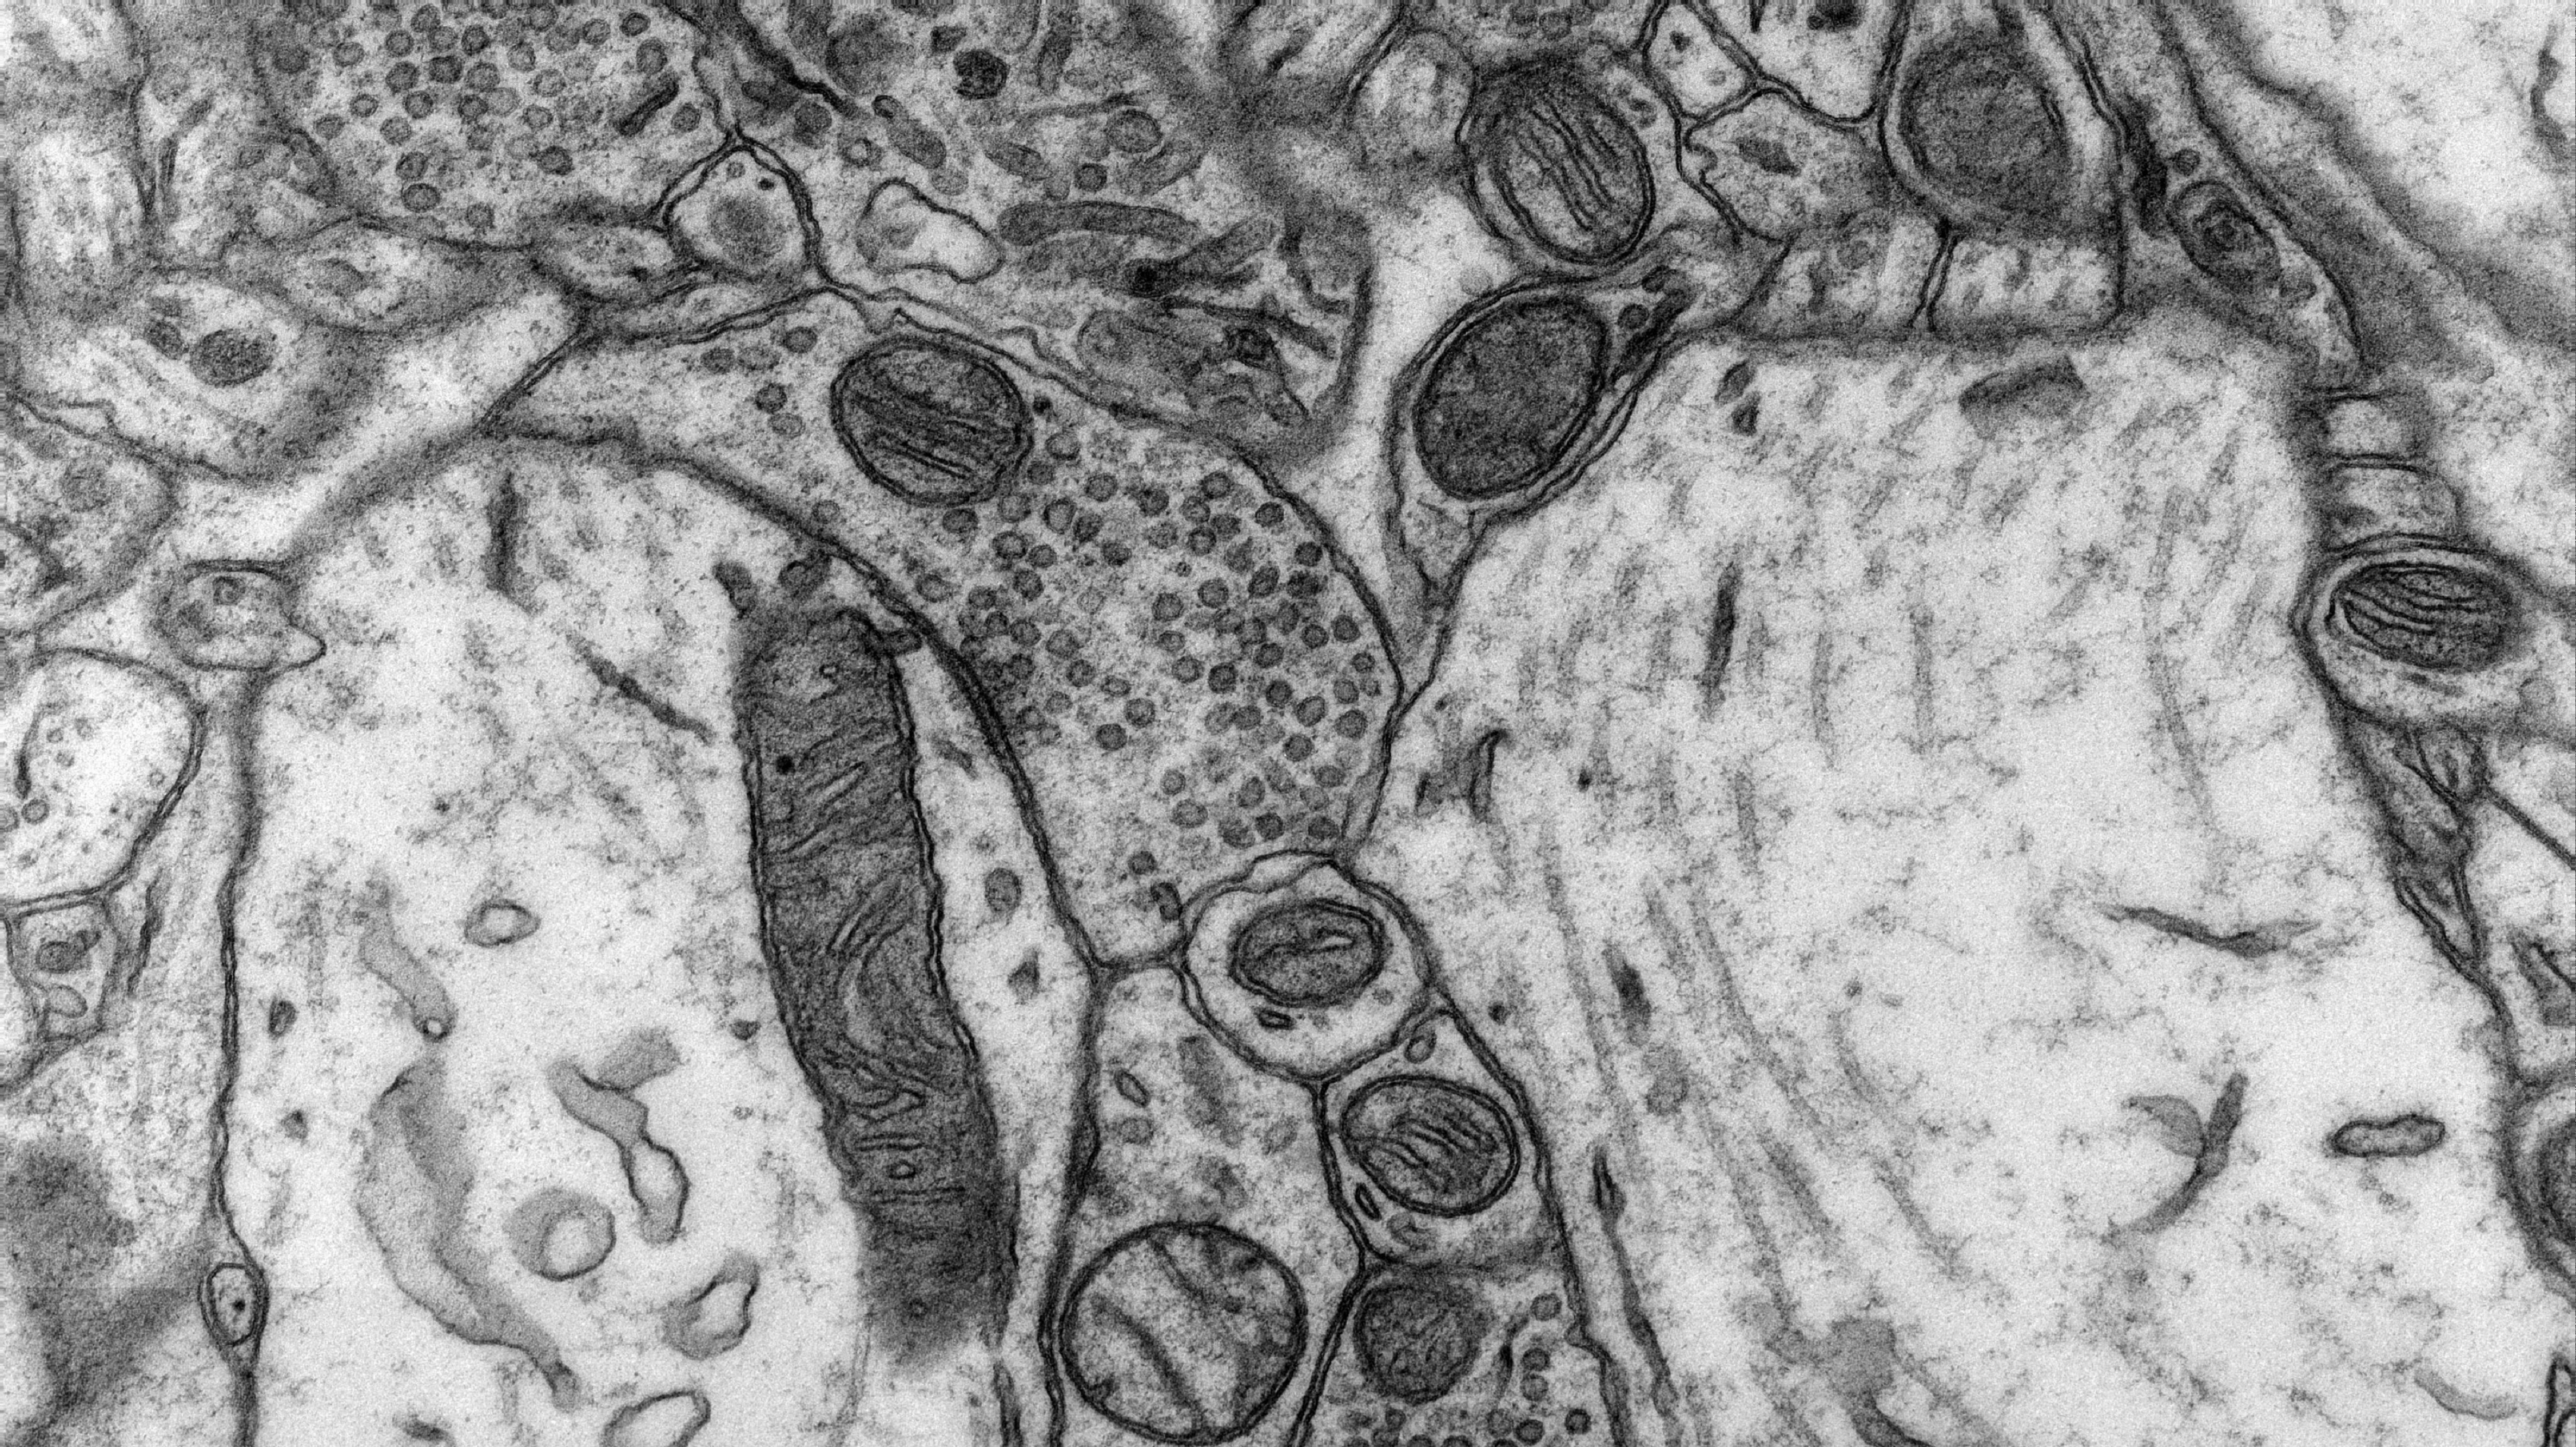

Los experimentos pusieron de relieve el papel en estos procesos de un área del cerebro conocida como núcleo accumbens, durante mucho tiempo asociada a la motivación, la recompensa y la depresión (en seres humanos también). En las ratas con alta ansiedad, que al competir socialmente alcanzaron un estatus social más bajo en el grupo, esta región cerebral mostró un metabolismo energético reducido.

Este hecho implica que las mitocondrias -orgánulos celulares que se encargan de la respiración y la producción de energía de la célula- presentaban una funcionalidad más baja en las ratas ansiosas que en las ratas más relajadas.